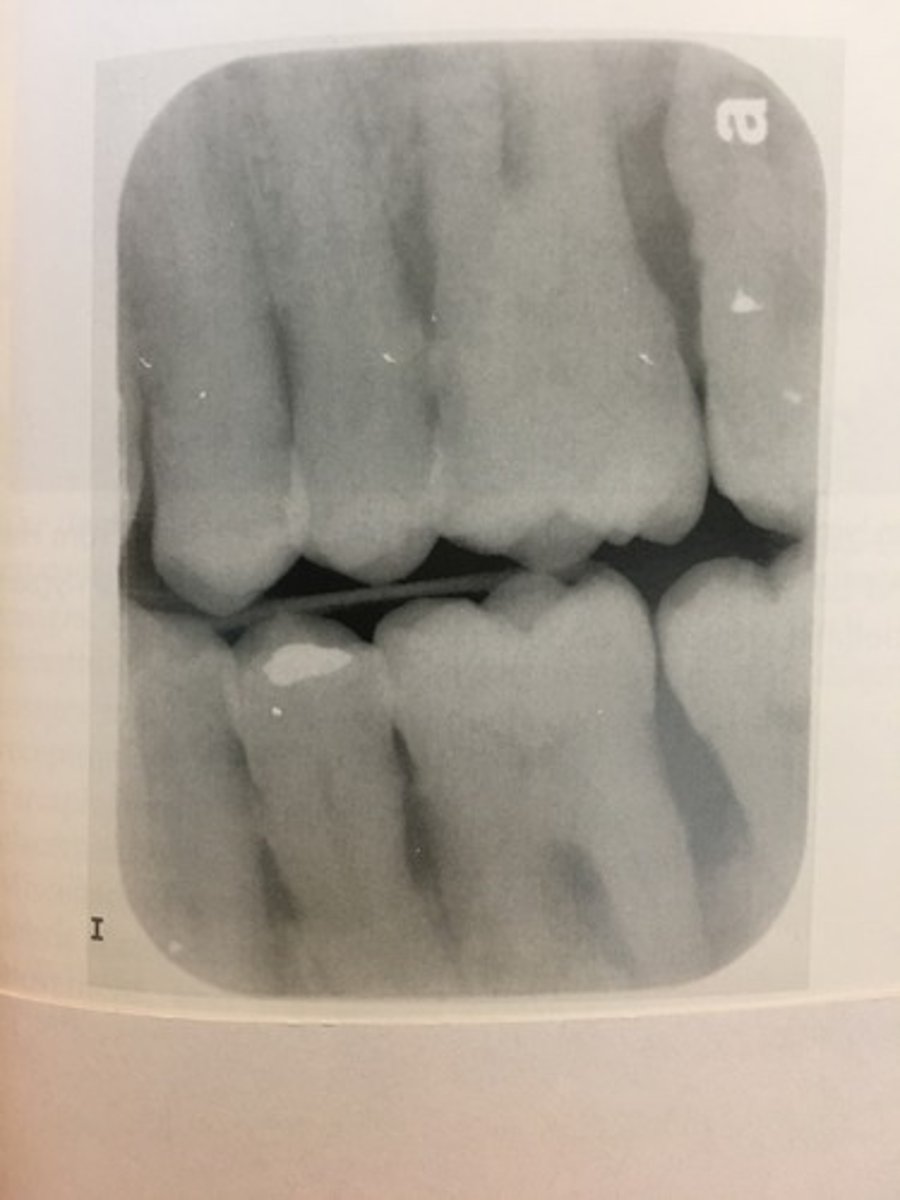

Dropped receptor corner

The occlusal plane appears tipped or tilted.